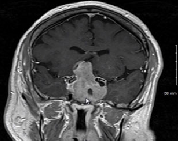

37岁的女士珍妮(化名),近几个月来,月经紊乱,并且经常感到腰背跳痛。然后到当地的Lariboisiere医院检查,术前磁共振成像(MRI)显示位于蝶鞍中央的9mm微腺瘤,被诊断为垂体瘤,月...

垂体瘤 是常见的颅内肿瘤。对于垂体瘤的治疗,药物治疗或经蝶窦手术通常是泌乳素瘤和其他腺瘤亚型的一线治疗方法。由经验丰富的外科医生进行蝶窦手术,治愈率为60-80%。视肿瘤的...

切除垂体肿瘤的手术通常由神经外科医生进行,这是一名专门治疗包括大脑和脊柱在内的中枢神经系统疾病的外科医生。切除垂体肿瘤较常见的方法是经蝶入路,外科医生通过鼻子插入...